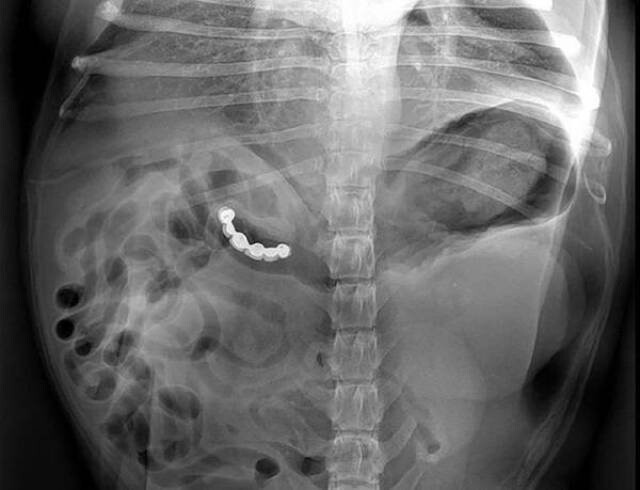

11. Английская булавка